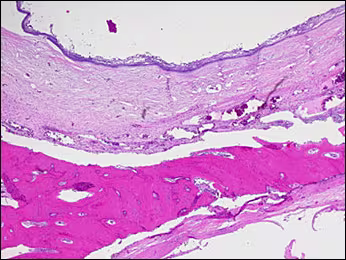

Histologic examination revealed curetted fragments of a hard and soft tissue specimen with the architecture of a cyst. The lumen of the cyst was lined by epithelium and was supported by an underlying connective tissue wall of fairly uniform thickness. In many areas, a rim of trabecular bone encased the cystic lesion. (Figure 10)

Figure 10. The lumen of the cyst was lined by epithelium and was supported by an underlying connective tissue wall of fairly uniform thickness. In many areas, a rim of trabecular bone encased the cystic lesion.